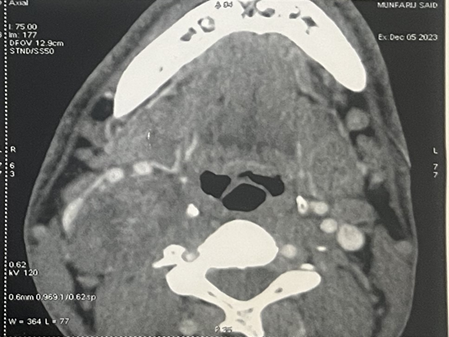

On the cervical CT scan, a voluminous mass well

limited to the right side of the cervix with carotid and jugular vascular

contact, the site of some calcification without contrast in arterial washout or

typical intercarotid topography, suggesting a glomus origin. (Figure 1).

Figure 1: CT imaging of a vagal schwannoma (red arrow) on the right

cervical side: (A) sagittal (B) axial and coronal (C) view.